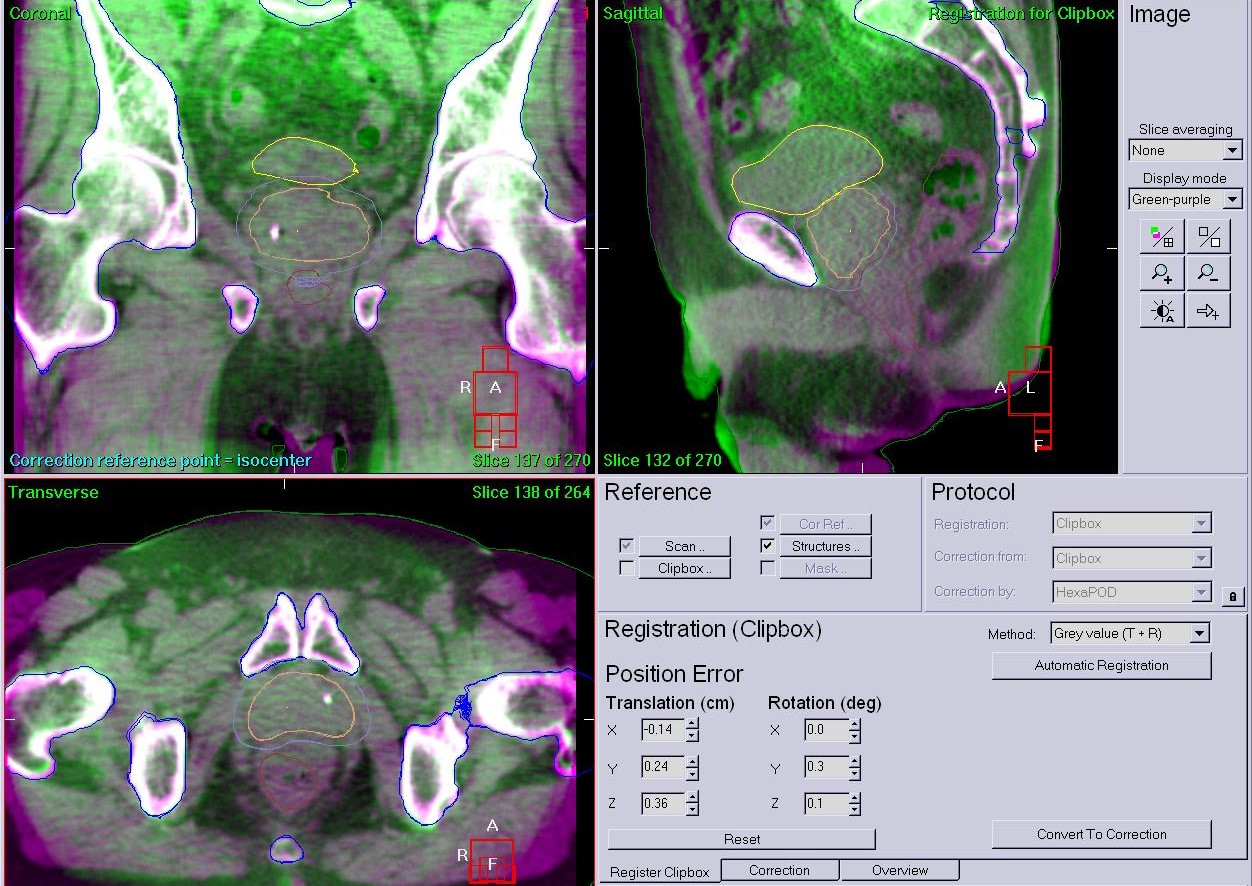

■画像誘導放射線治療(IGRT)

治療を行う際には、体に描いたマーキングを参考に毎日同じ姿勢で寝台に寝ていただき治療を実施します。しかし体の中の臓器、病変は毎日同じ位置にあるとは限りません。そのため治療開始直前に治療の寝台の上でCT撮影を行い、正確に位置の修正を行うことで、より精度の高い治療を実施する事が可能です。